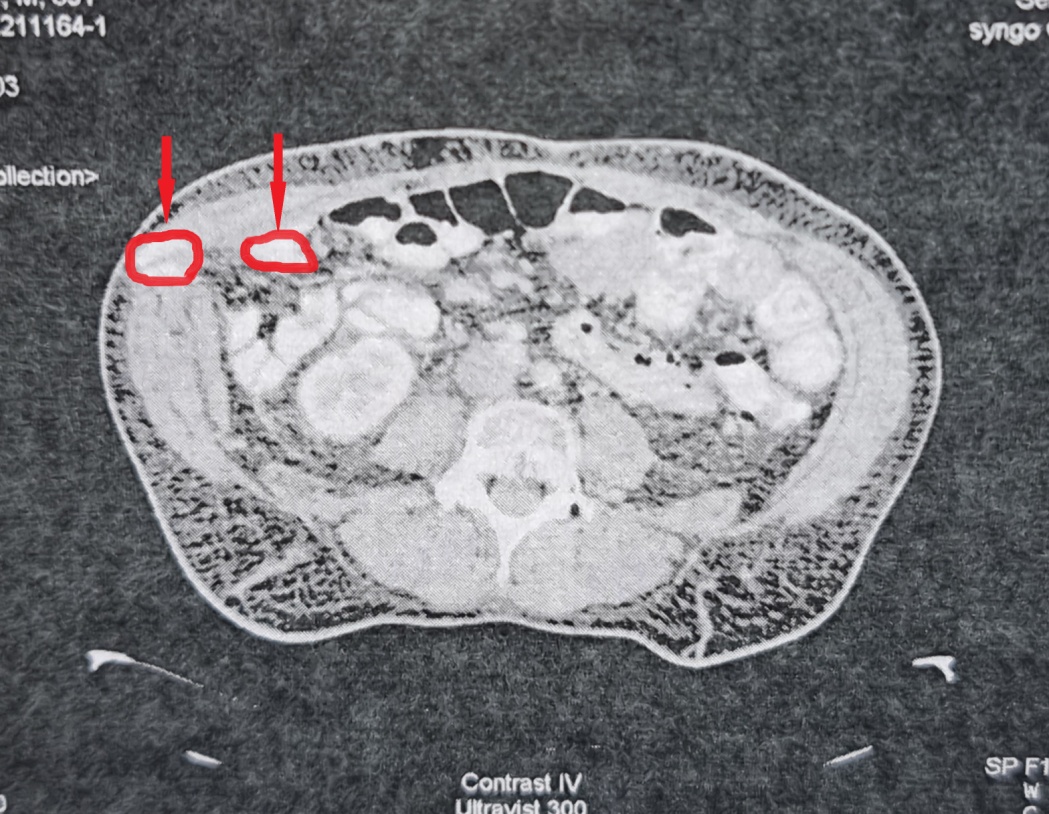

CT κοιλίας. Μεταστατικές εστίες στους σκελετικούς μύες δεξιά (κόκκινα βέλη) (Ευγενική παραχώρηση Dr. V. Penopoulos)